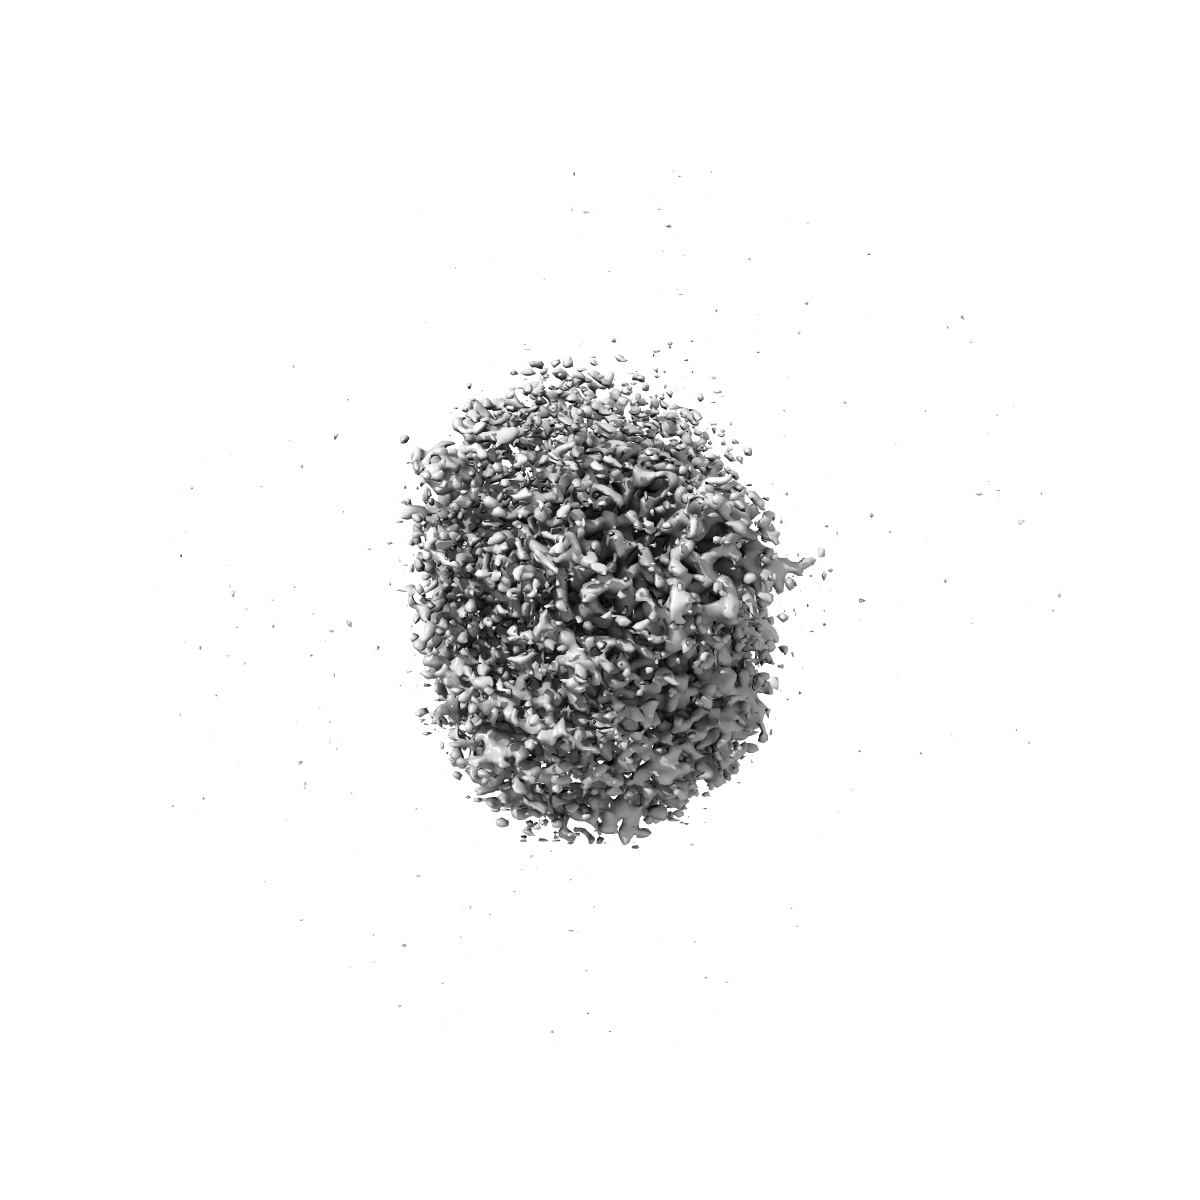

Cryo-EM structure of human TauT in presence of taurine, determined in an inward-facing occluded conformation

Sample: Complex of human Taurine Transporter with taurine

Transport and inhibition mechanism for human TauT-mediated taurine uptake.

Chao Y, Zhou Z, Xia H, Yang C, Li T , Tang YQ, Shu Y , Ba Q, Hong J , Li D , Qu Q

(2025) Cell Res , 35 , 381 - 384